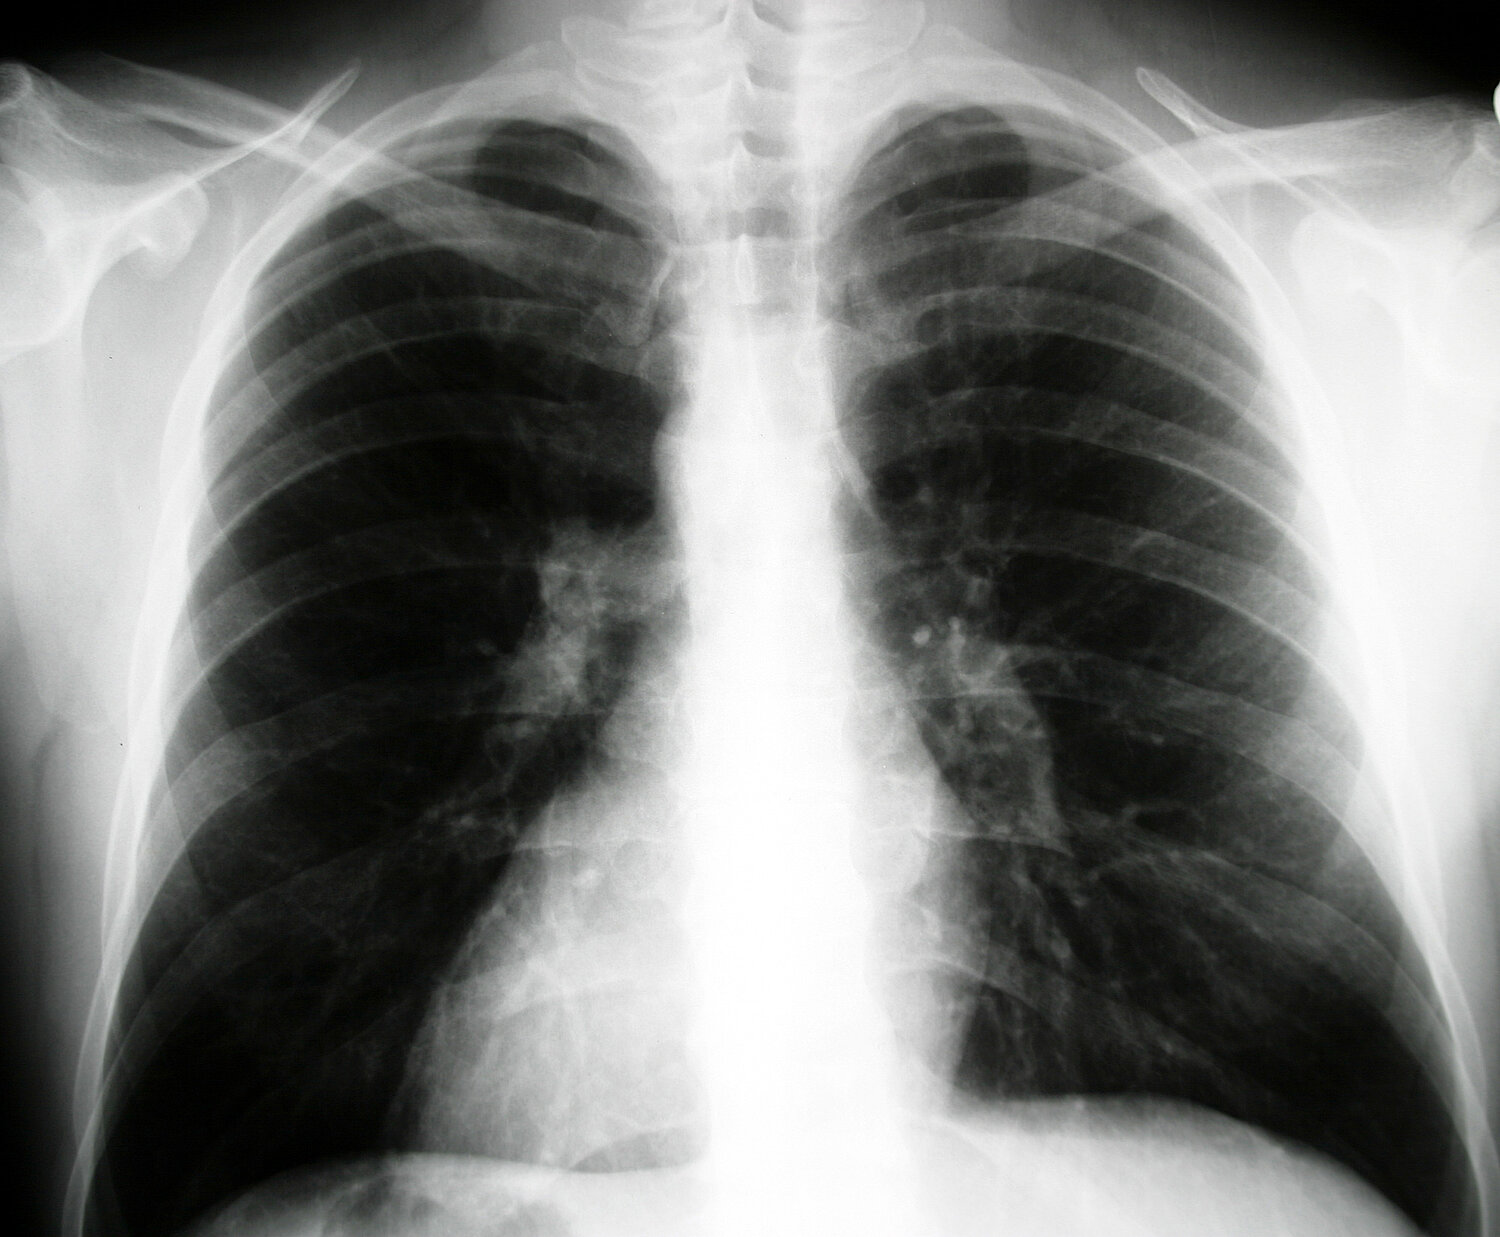

Feinstaub PM10 kann tief in die feinsten Verästelungen der Lunge eindringen und von dort zum Teil in die Lymph- und Blutbahnen, da die Filterwirkung des Nasen-Rachenraumes für so kleine Partikel nicht ausreicht. Ultrafeine Partikel gelangen bis in die Lungenbläschen (Alveolen) und werden von dort nur sehr langsam oder gar nicht wieder entfernt (Staublunge).

Feinstaub verursacht in den Atemwegen lokale Entzündungen und kann so zu schwerwiegenden Gesundheitsschäden führen: Husten, Atemnot, Bronchitis und Asthmaanfälle; Verstärkung von Allergiesymptomen; Atemwegs- und Herzkreislauf-Erkrankungen; vorzeitige Todesfälle und Lungenkrebs.

Die zerklüftete Struktur der Feinstaub-Teilchen ermöglicht außerdem eine Anlagerung von Schadstoffen an deren Oberfläche. Das Ausmaß der Auswirkung auf die Atemwege hängt demnach von der Toxizität der Partikel und deren Größe ab: je kleiner ein Partikel ist, desto tiefer kann es in die Lunge eindringen.